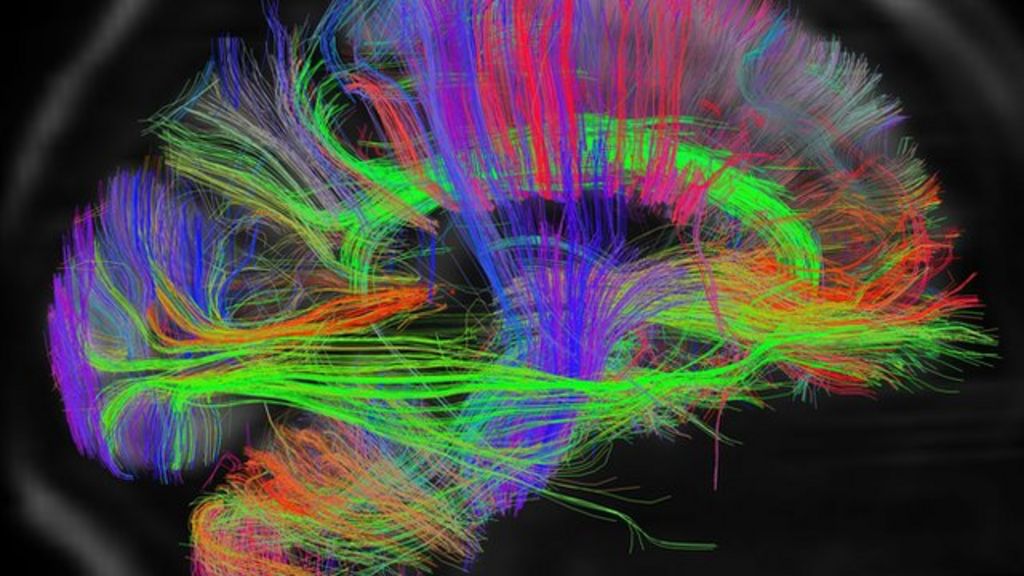

Коннектом мозга: визуализация связей и нейронных путей